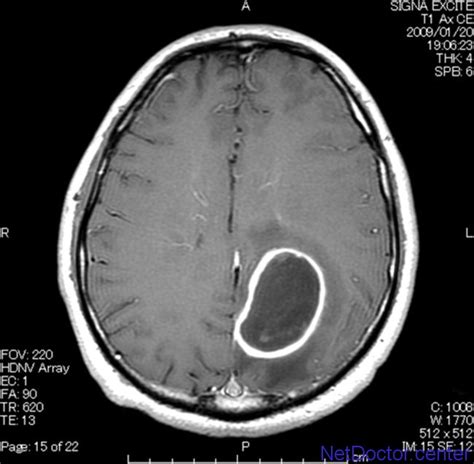

【病例】脑脓肿1例ct及mr影像表现

【病例讨论】又一例环状强化,结果公布:脑脓肿 [病例帖]

"套环征"在脑脓肿诊断中的意义_病理_扫描_低密度